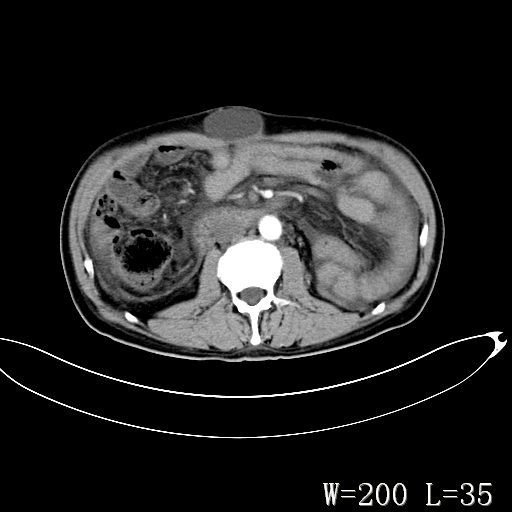

男,52岁,门脉高压断流术后1年,发现腹部肿物2月。

1)前腹壁中线区(脐上方)囊性占位性病变,考虑淋巴囊肿。2)腹水。